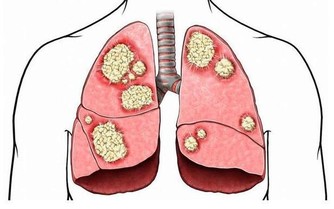

傷肝習慣一:抽煙

抽煙傷肺我們聽多了,為什麼也會傷肝呢?

因為香煙中的尼古丁是通過肺和肝臟代謝的,如果大量的吸煙,肝臟解毒的工作負擔會進一步加重。而且,尼古丁會使人興奮,導致血管收縮,並且增加血液粘稠度。這樣就會使肝臟的供血減少,使肝臟無法獲取營養。